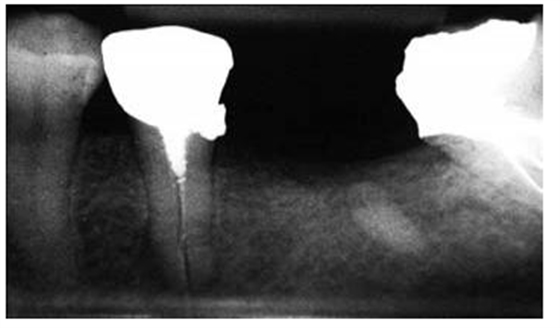

圖4:下頜第二前磨牙的根尖片,經(jīng)由螺紋樁進行修復(fù),導(dǎo)致根折

5:下頜第二磨牙牙根穿孔的根尖片,樁道預(yù)備的器械未與根管壁相平行

研究結(jié)果表明牙根折斷是樁核修復(fù)失敗的第二個最為常見的原因。多個原因已經(jīng)被證實與牙根折斷潛在相關(guān),其中包括大直徑的樁修復(fù),短樁和帶螺紋的樁(圖 4)。臨床上推薦樁的直徑不能超過牙根直徑的1/3,并且樁直徑應(yīng)當與牙根的平均尺寸成比例地相關(guān)。

對于牙體解剖、牙根結(jié)構(gòu)、形態(tài)及其變異的良好理解,同時使用恰當?shù)念A(yù)備方向,能夠幫助牙醫(yī)在樁道預(yù)備過程中避免出現(xiàn)過多的切削牙體組織和牙根穿孔。預(yù)備樁道時,器械的方向必須與根管的方向相平行(圖 5)。